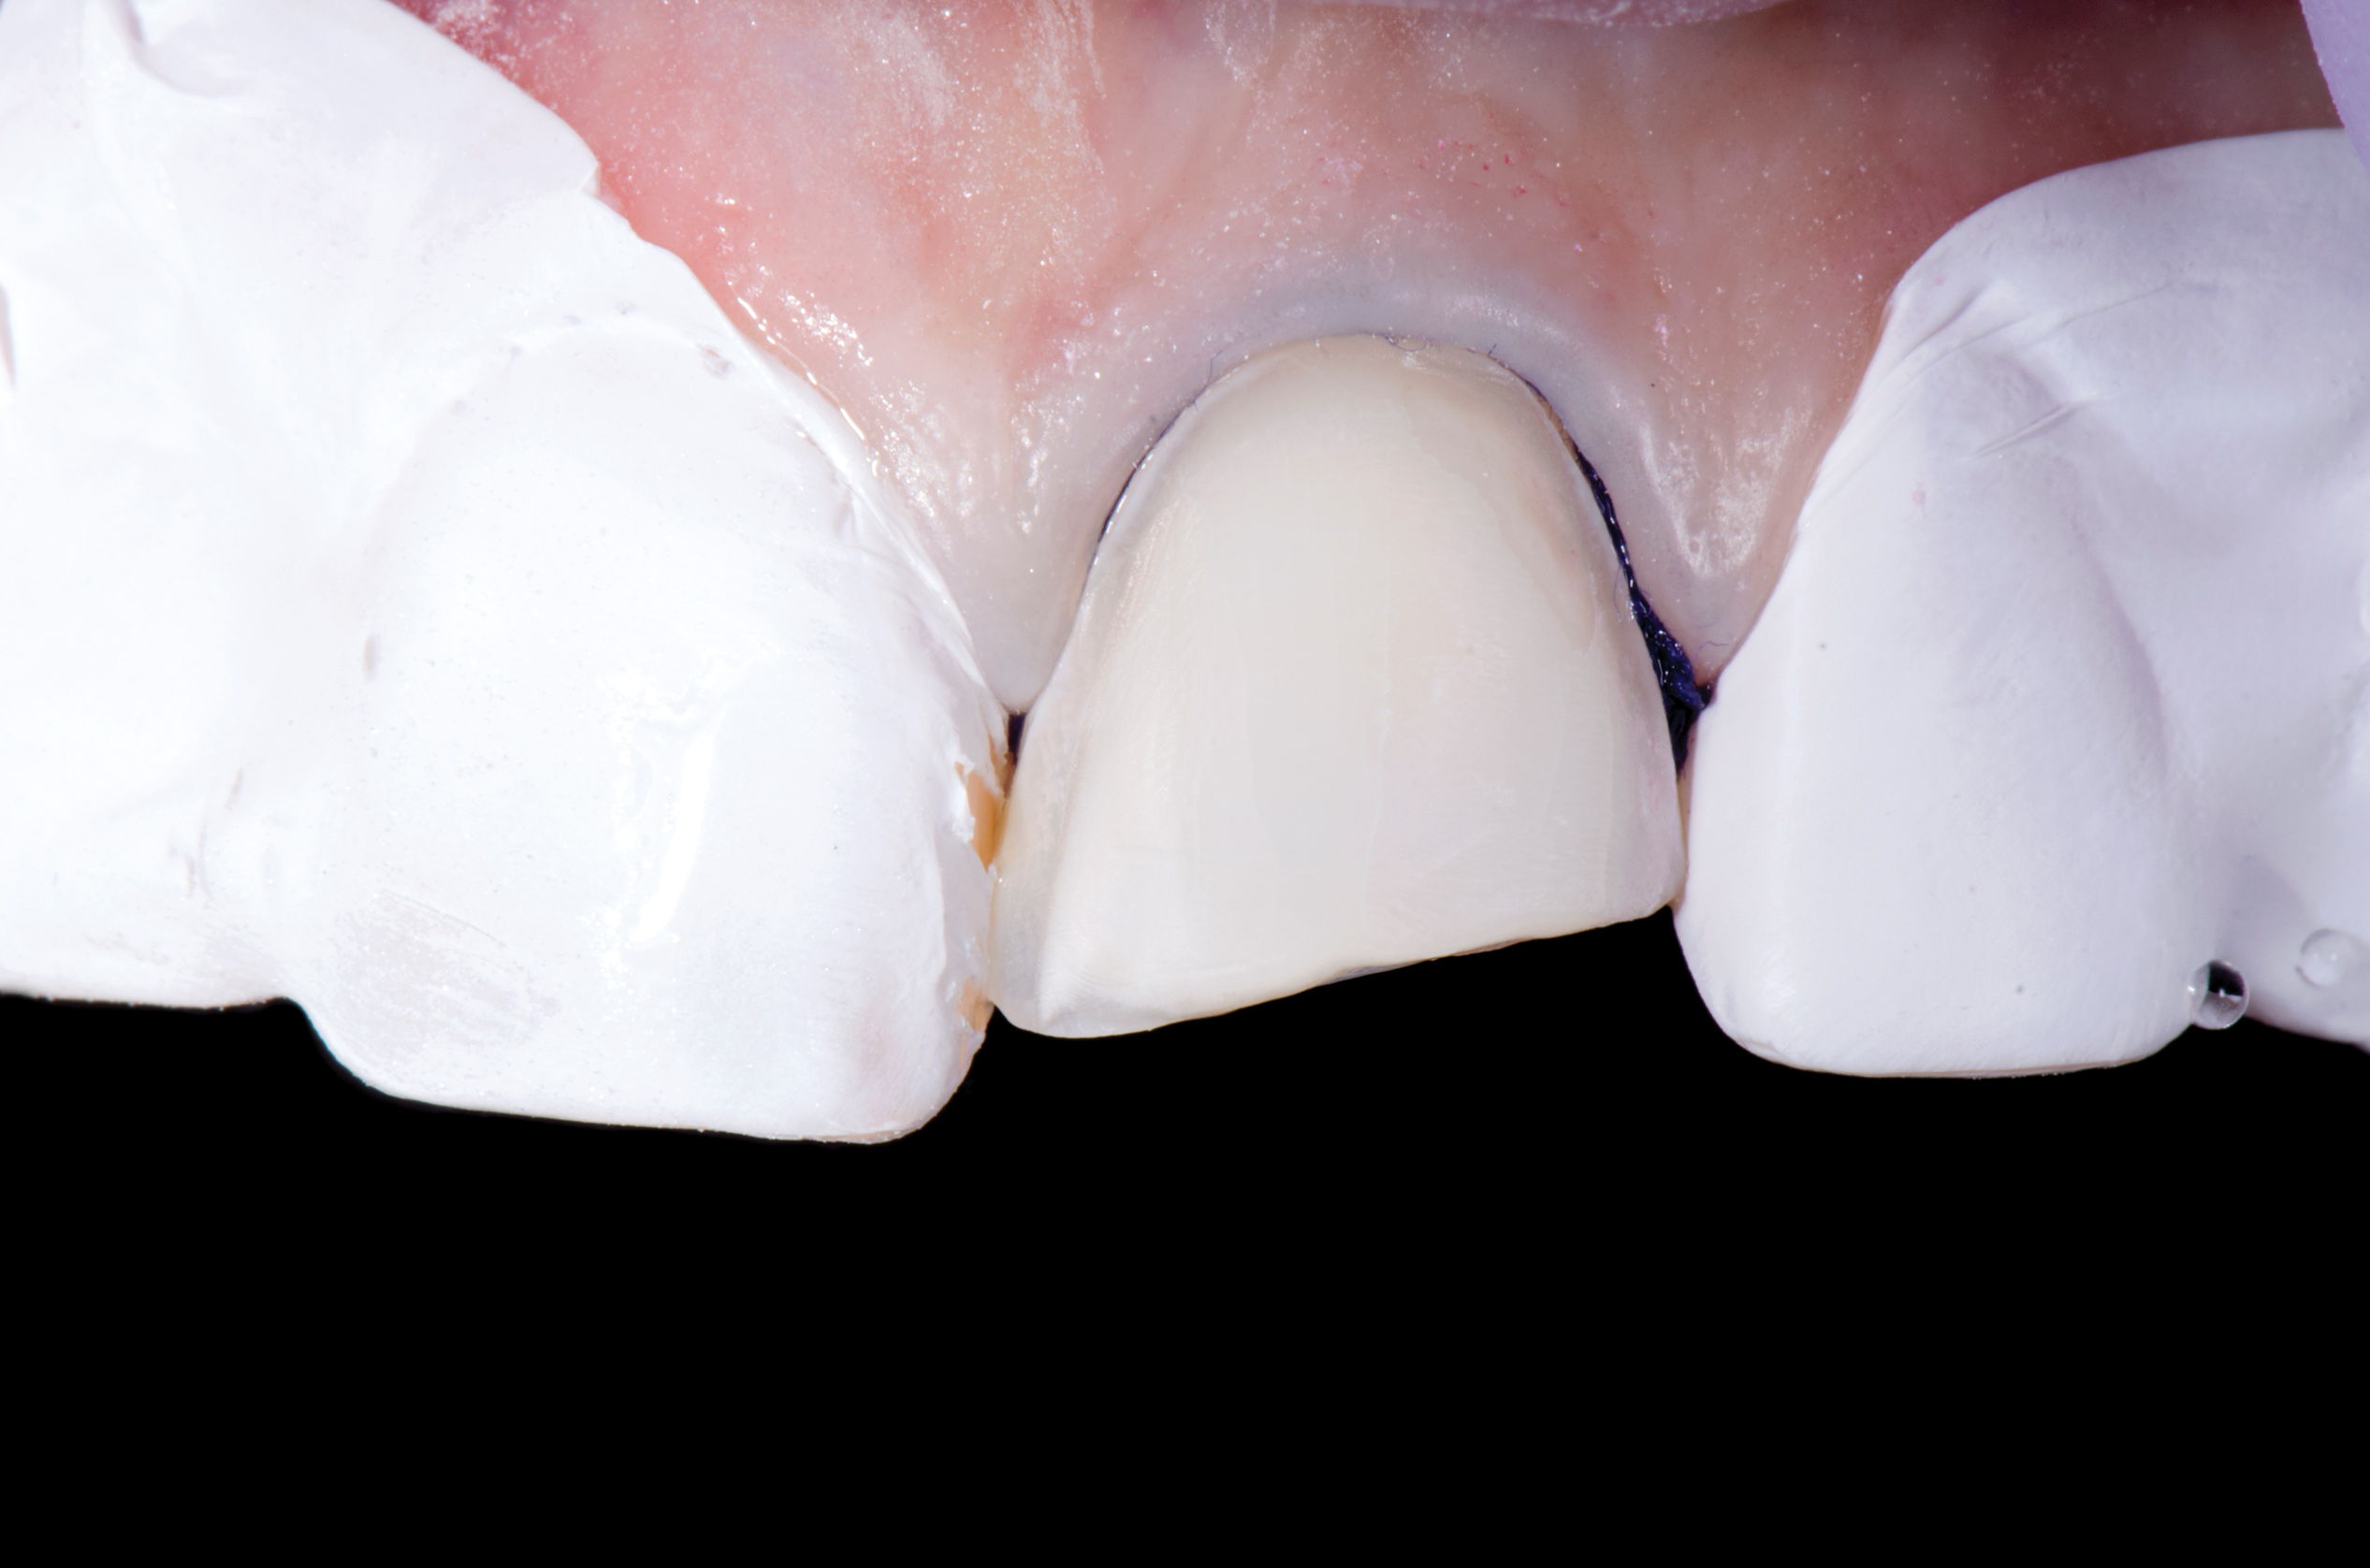

Fig 12. Matte surface of clean enamel after air abrasion prior to bonding.

Figure 12